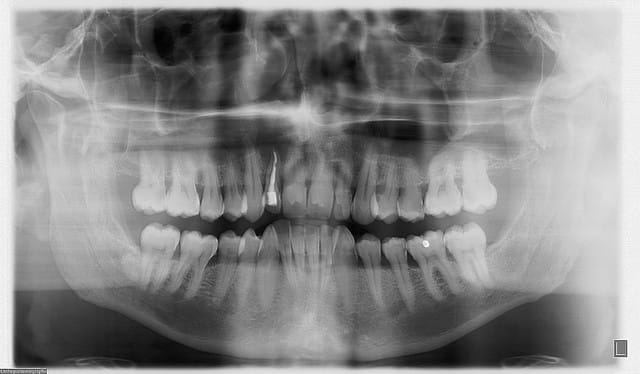

en 1997...ce patient vient pour un contrôle...quelques soins à faire...et découverte à la pano d'une lésion sur 12...

endo...et rdv 6 mois plus tard pour contrôler l'évolution...jamais honoré...

ce patient revient...13 ans plus tard..."docteur, y a ma dent qui bouge...faites quelque chose..."

pano....youpie...scan...et là je crois qu'on décroche le ponpon...

super sinus...bien sûr la dent est condamnée...mais vous feriez quoi pour avoir une chance de planter dans quelques mois...ou du moins éviter un "énorme" défaut osseux qui sera difficilement gérable d'un point de vue esthétique...???

t'as vu la taille du kyste??? il va jusqu'au sinus et se prolonge derrière la 11...la 12 ne tiens que par son ligament palatin...

un ptit zoom sur la pano...en renforçant le contraste...

pour D57...voussure vestibulaire...je sais pas trop s'il reste une corticale...ou si oui ultrafine...

le risque...perforation du sinus si la membrane kystique y adhère fortement...

je pensais tenter une sorte de ROG...en tapissant le fond (vers le sinus) avec une membrane collagène, et une autre vestibulaire au cas où il n'y ait plus d'os...

la question est plutôt...que mettre entre...

rien, des éponges hémostatiques, du biomat (lequel???biooss??) voir une membrane titane pour bien maintenir le volume???